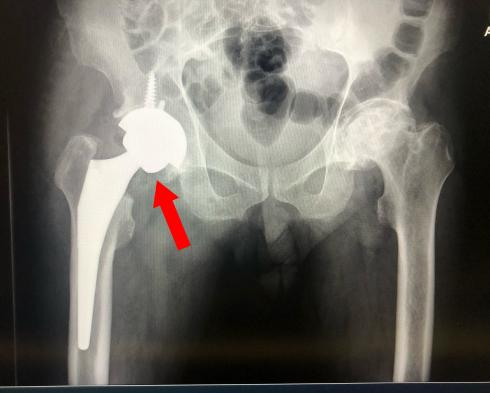

09/04 2025我院钱宇教授团队在国际顶尖期刊发表系列研究成果

近日,浙江省中医院(浙江中医药大学附属第一医院)骨伤医学中心钱宇教授团队连续在国际顶级期刊《Advanced Functional Materials》(双一区TOP,IF=19.0)和《Bioactive Materials》(双一区TOP,IF=20.3)发表最新研究成果,在感染性创面修复与骨质疏松性骨缺损再生两大领域实现原创性突破。